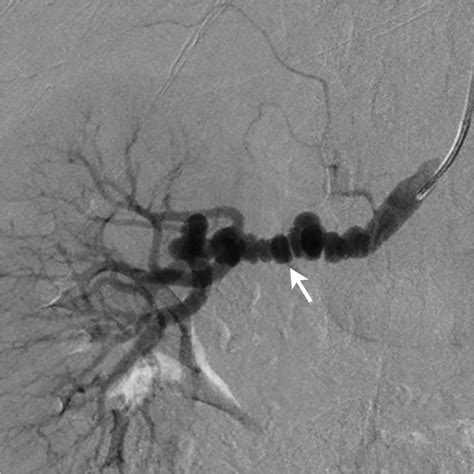

Image:Fibromuscular Dysplasia of the Renal Artery-Merck Manual

Renal denervation in fibromuscular dysplasia | BMJ Case Reports